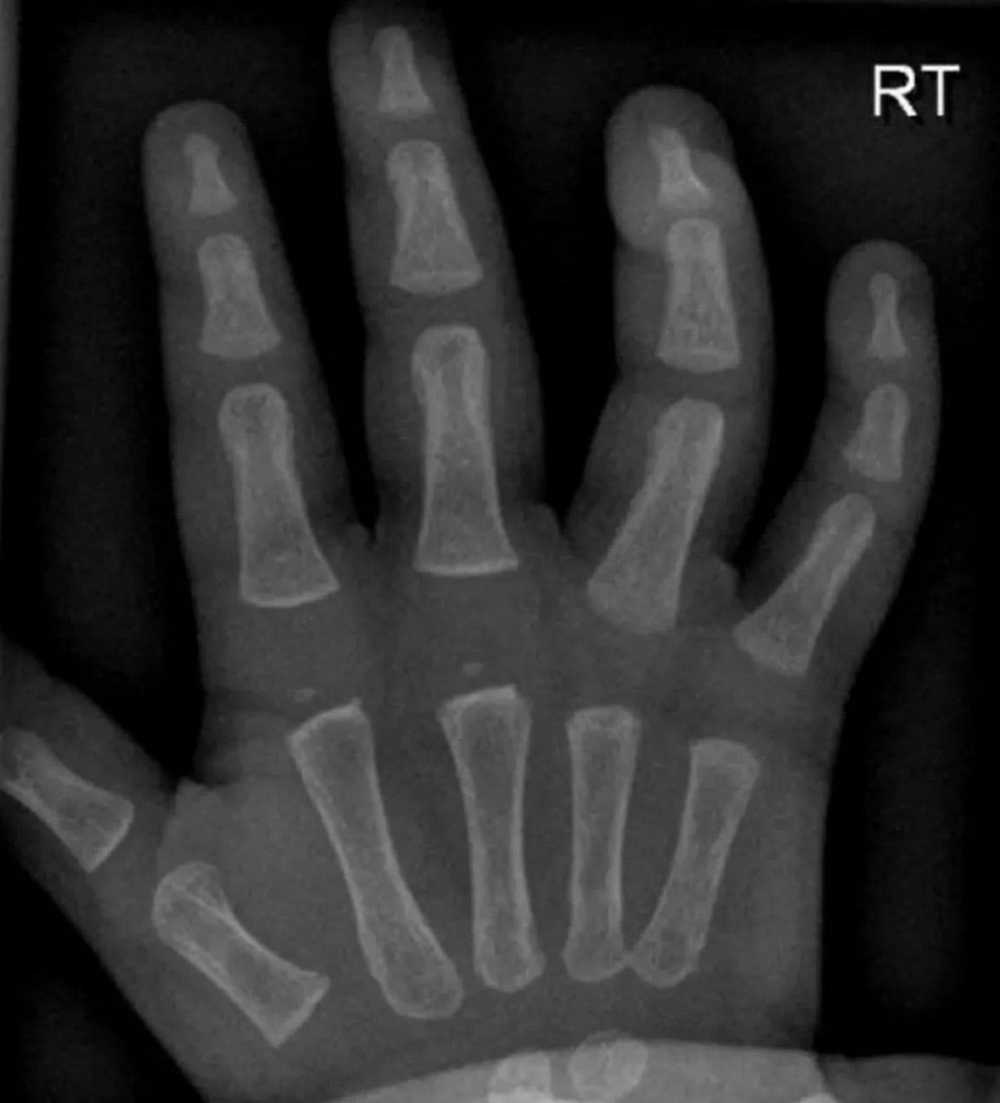

애기들이 통통한 이유 졸귀임요ㅋㅋㅋ 작성자 정보 백억랜드 쪽지보내기 메일보내기 자기소개 아이디로 검색 전체게시물 쪽지보내기 메일보내기 자기소개 아이디로 검색 전체게시물 작성 작성일 2025.04.25 07:22 컨텐츠 정보 690 조회 19 추천 목록 본문 19 추천 관련자료 이전 전설의 포상휴가 12개월 받은 군인 작성일 2025.04.25 07:35 다음 mbti 평생 함께 하고픈 사람 순위 작성일 2025.04.25 07:03 댓글 0 등록된 댓글이 없습니다. 로그인한 회원만 댓글 등록이 가능합니다. 목록